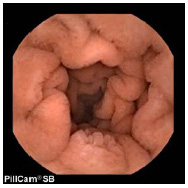

PillCamR SB 2 の画像

PillCam® SB 2 の画像

従来製品と比べ,画質が飛躍的に向上し,視野角を拡大させることにより,撮像面積が2倍以上になった。また自動調光機能の採用により,近部から遠部まで鮮明な画像の撮影が可能となる。

・視野角が140度から156度にアップし,撮像面積が大幅に拡大

・多層化レンズ採用により,画質が飛躍的にアップ

・自動調光機能採用により,近部から深部まで鮮明